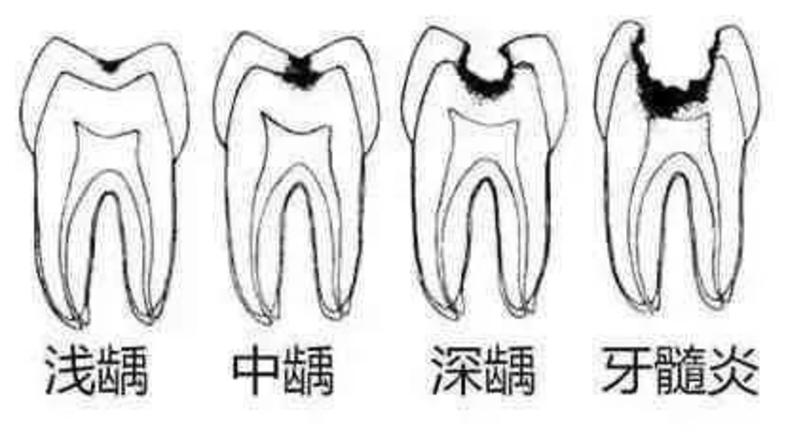

细菌深度决定龋齿的程度

浅龋齿:细菌到达牙釉质层,患者没有明显感觉

中龋齿:细菌到达牙本质,一开始会感觉酸痛,一段时间后酸痛感就会消失

深层龋齿:细菌到达牙本质深层,接近牙髓,咬东西时会感到刺痛,疼痛感会反复出现.

牙髓炎:细菌进入牙神经,患者会有剧烈的疼痛感。如果不及时治疗,细菌会杀死牙神经